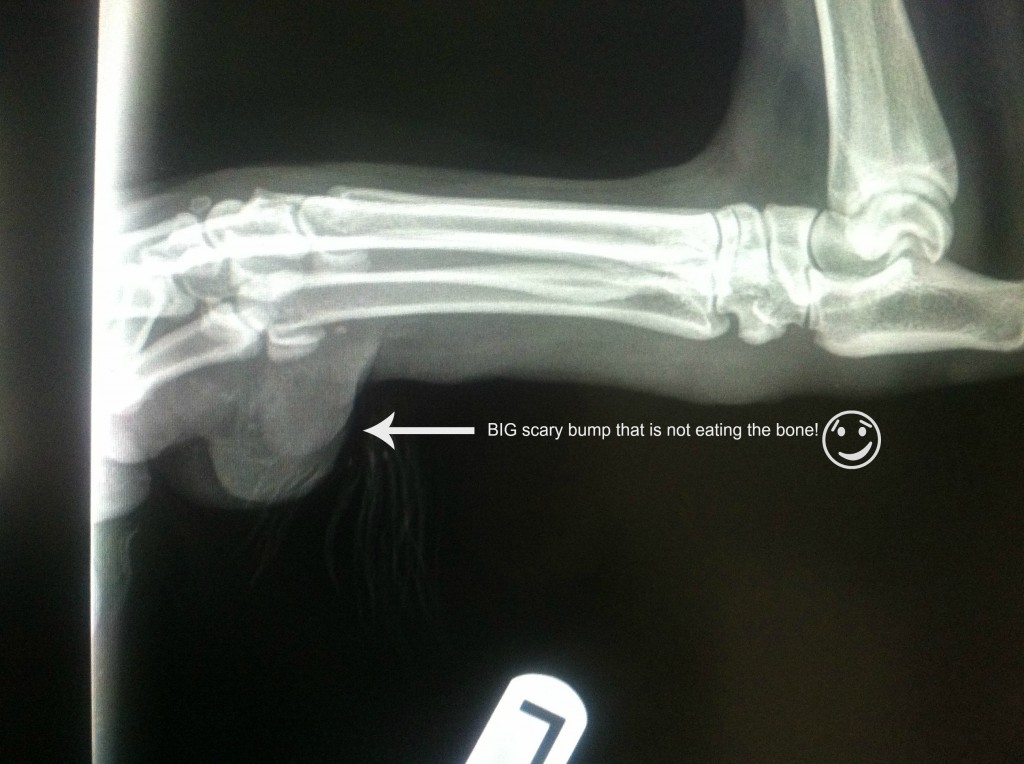

And just so I can defend my craziness last week, here is an image of the big scary bump on his left rear leg.